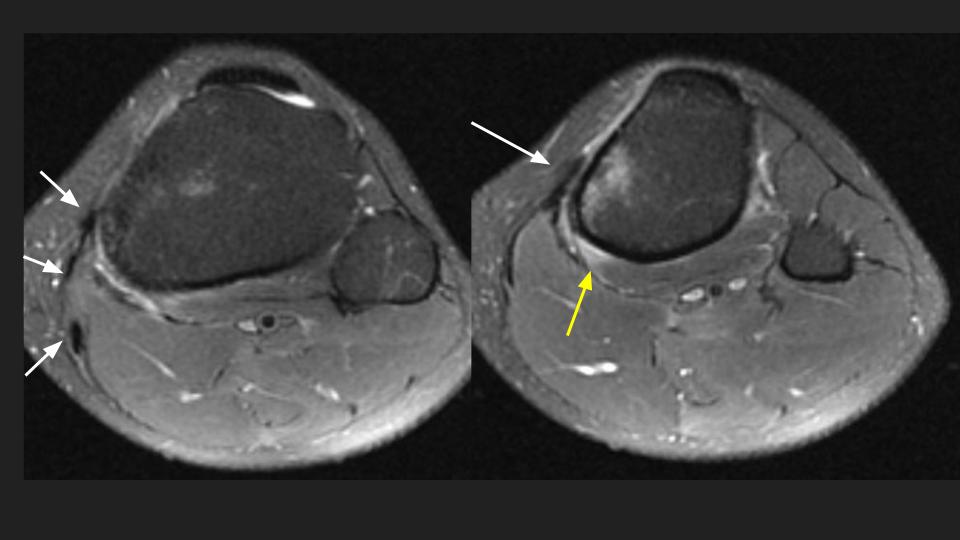

27F athlete with 4 weeks symptoms of pes anserine bursitis

There is subcortical marrow edema along the medial proximal tibial metadiaphysis, more prominent on PDFS, but faintly visible on T1w. There is superimposed periosteal edema with minimal pes anserine bursal edema (pes tendons indicated by white arrows) and minimal reactive edema extending into the medial popliteus muscle (yellow arrow). Clinically there is no surprise this was presumed to be pes anserine bursitis. I wonder how many cases of tibial stress reaction (stress related BME and periosteal edema / impending stress fracture) we or our referring clinicians have misdiagnosed as pes bursitis and just injected with steroids.

tibial stress reaction